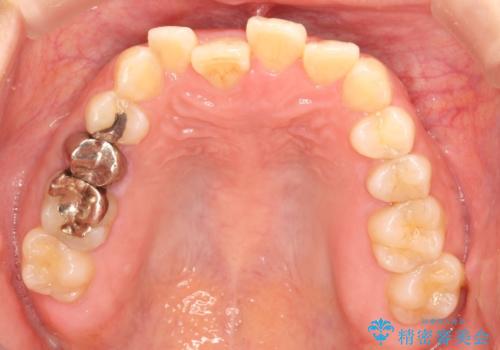

インビザラインにて矯正治療後の前歯のセラミッククラウン治療

- 前歯の歯並びが気になるとのことで来院されました。

右上の1番目の歯が内側に入り込んでしまっており、その歯がの先端がすり減ってしまっていました。

インビザラインによる矯正治療で前歯の歯並びを改善し、セラミッククラウン装着により歯の形態の回復をする計画としました。